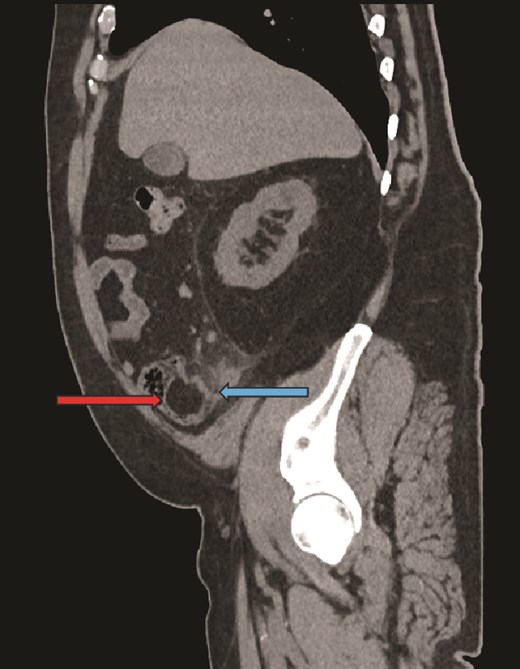

Computed tomography (CT) scan abdomen and pelvis was reported as follows: ‘Inflammatory phlegmon, fat stranding, free fluid, and reactive lymphadenopathy in the right iliac fossa. At the centre of the inflammatory phlegmon there is a dilated appendix with thickened walls. Small appendicolith at the base. Incidental note of a 3.2 cm caecal lipoma, which resides just below the ileocecal valve.’ (Figs 1–3).

Sagittal CT image, showing caecal lipoma (right arrow) and appendicitis (left arrow).